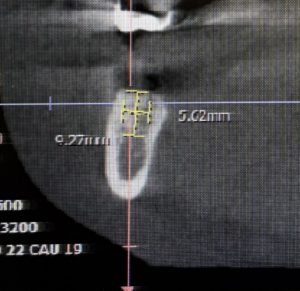

本日は右下7番の抜歯からインプラント植立になった方です。

ストローマン 直径5.5×6mm BLX このインプラントの特徴は骨との食いつきがいいことです この回はフラップレスオペになりました。